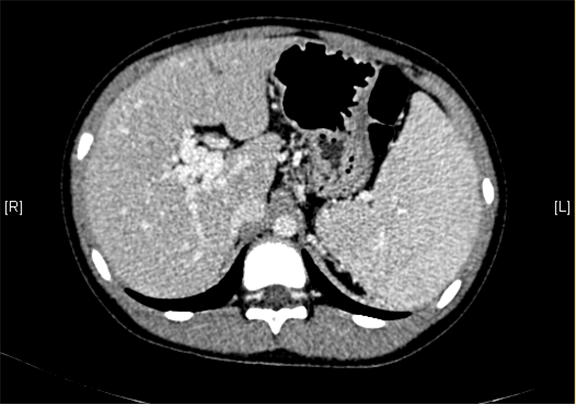

上腹部增强CT:门静脉主干走行迂曲、分支紊乱,考虑门静脉畸形可能性大,不除外门静脉海绵状变性。

术前CT检查:

动脉期

静脉期

平衡期